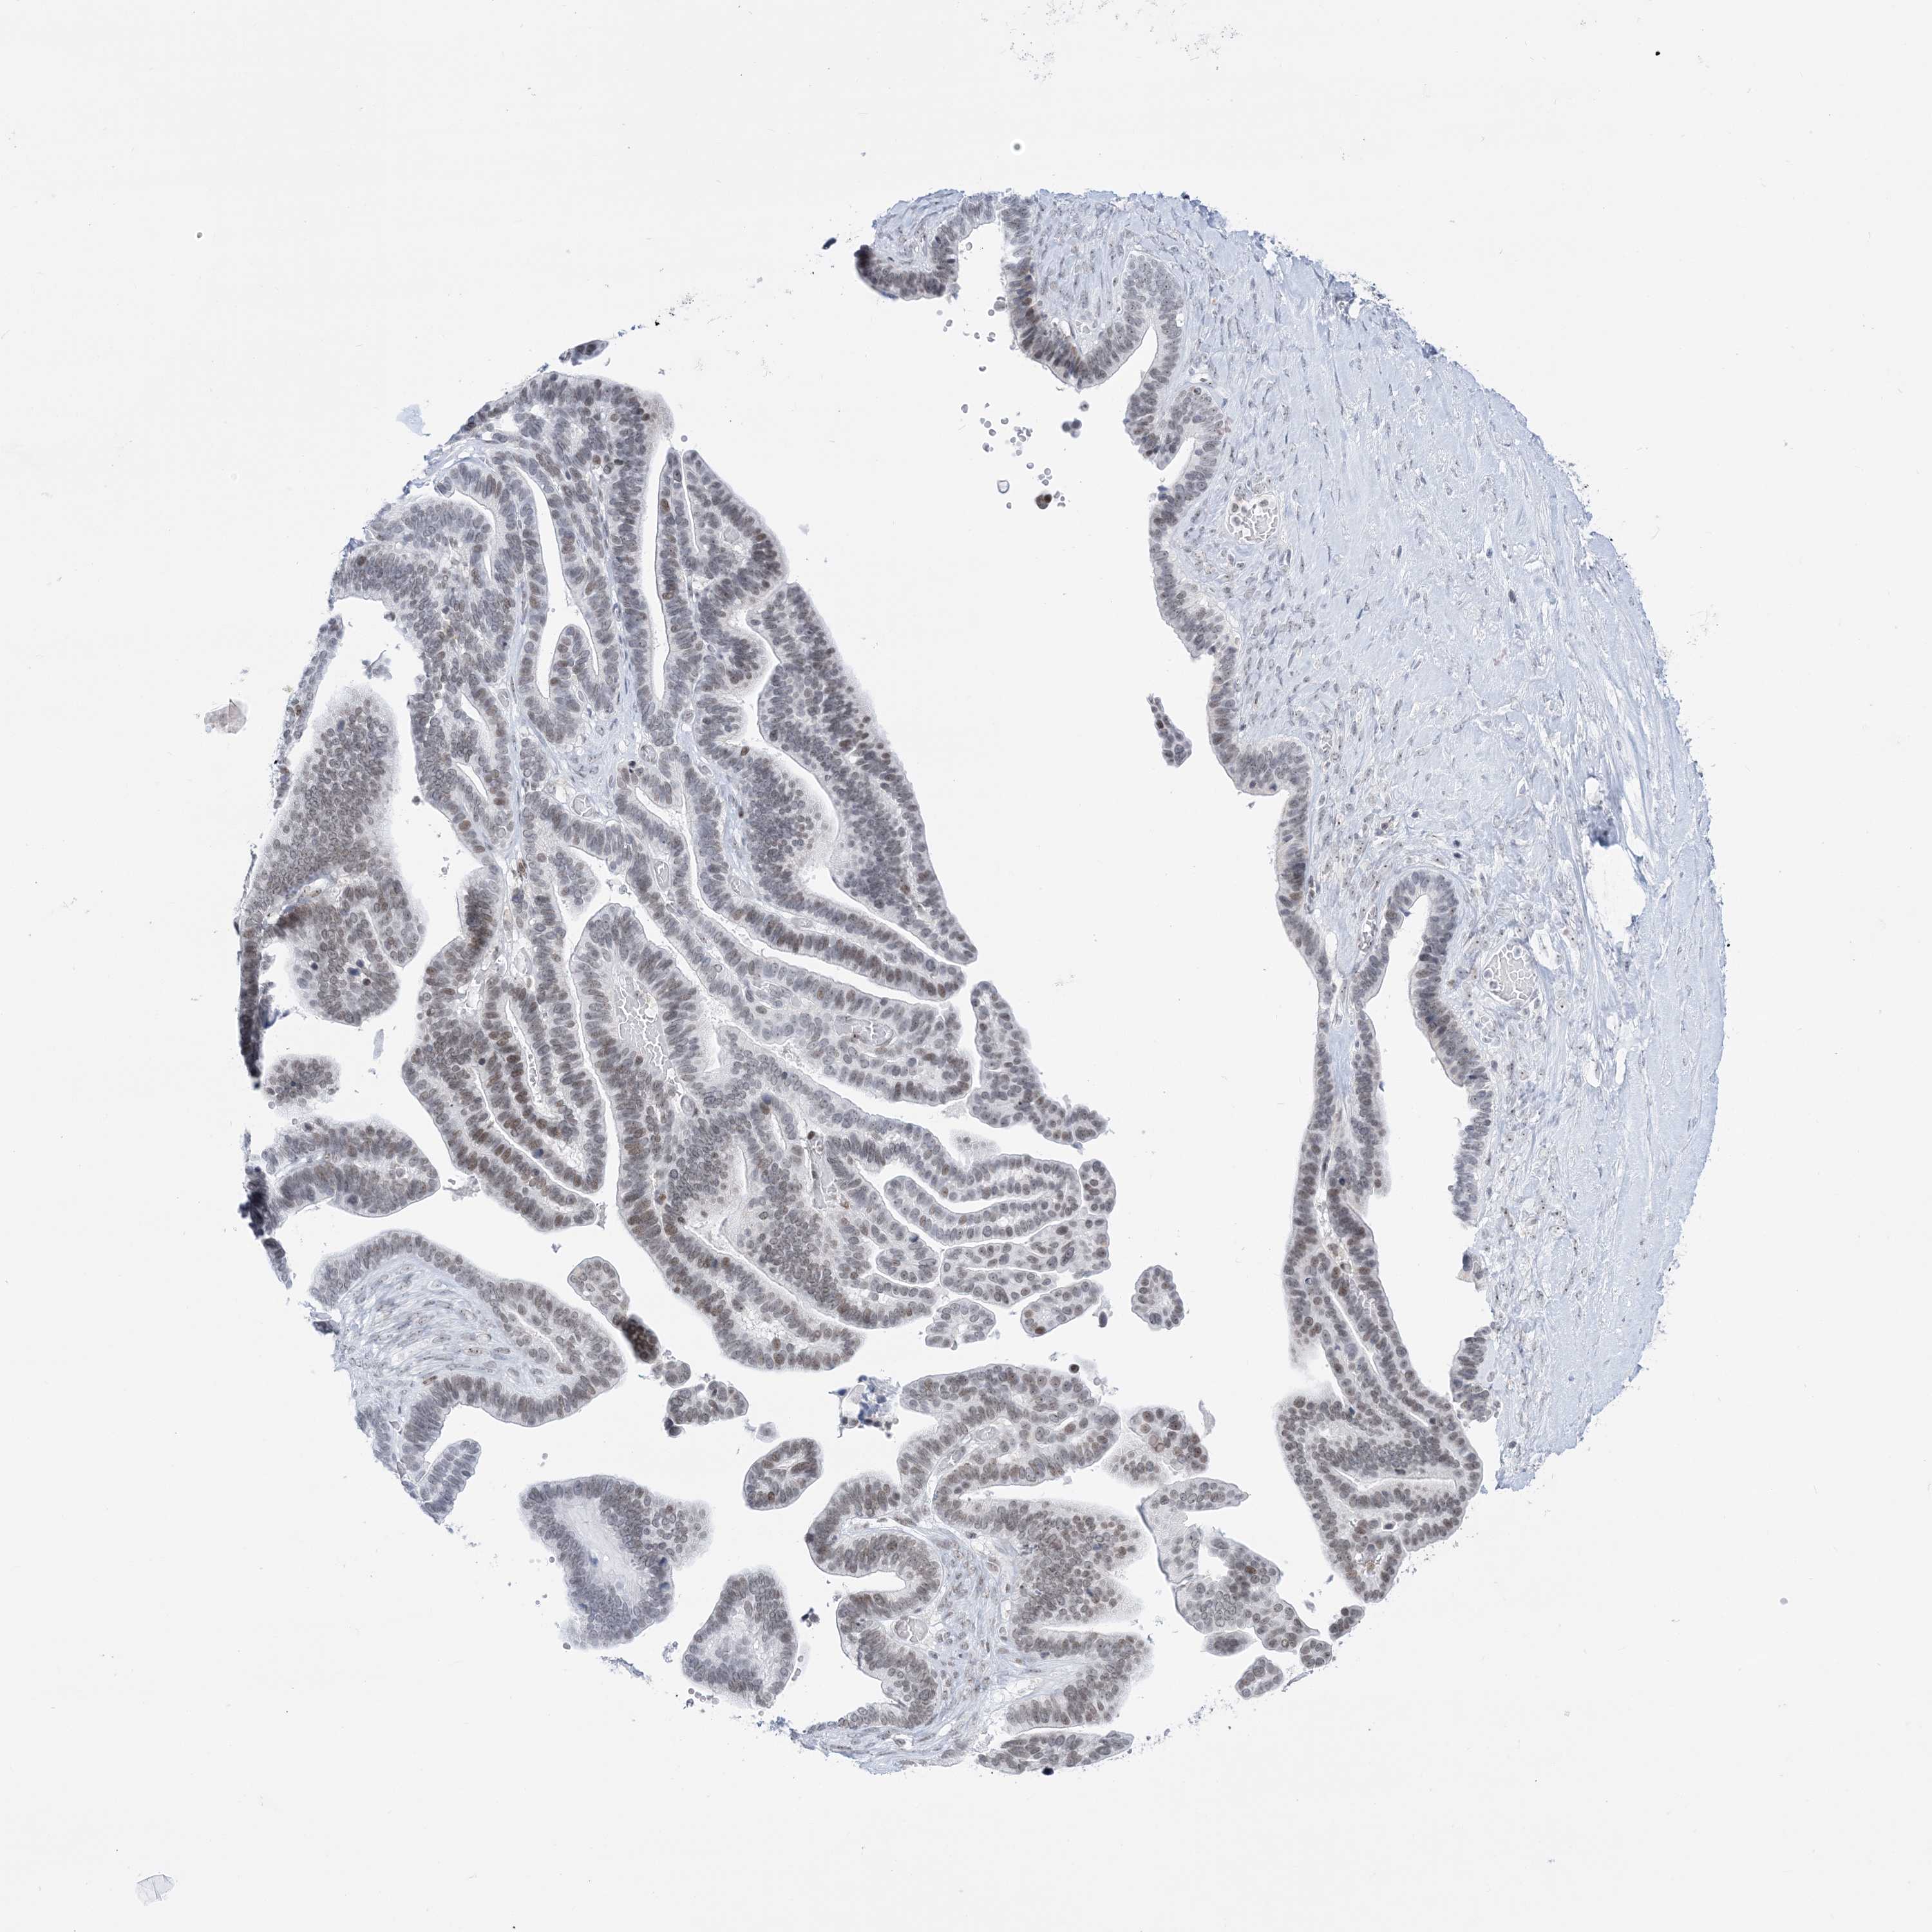

OVARIAN CANCER - Protein expressioni

A mouse-over function shows sample information and annotation data. Click on an image to view it in a full screen mode. Samples can be filtered based on level of antibody staining by selecting one or several of the following categories: high, medium, low and not detected. The assay and annotation is described here.

Note that samples used for immunohistochemistry by the Human Protein Atlas do not correspond to samples in the TCGA dataset.

Antibody stainingi

Antibody staining in the annotated cell types in the current human tissue is reported as not detected, low, medium, or high, based on conventional immunohistochemistry profiling in selected tissues. This score is based on the combination of the staining intensity and fraction of stained cells.

Each image is clickable and will lead to virtual microscopy that enables deeper exploration of all samples and also displays staining intensity scores, fraction scores and subcellular localization as well as patient and tissue information for each sample.

Antibody HPA036593

Cystadenocarcinoma, serous, NOS

Carcinoma, endometroid

Cystadenocarcinoma, mucinous, NOS

Carcinoma, NOS